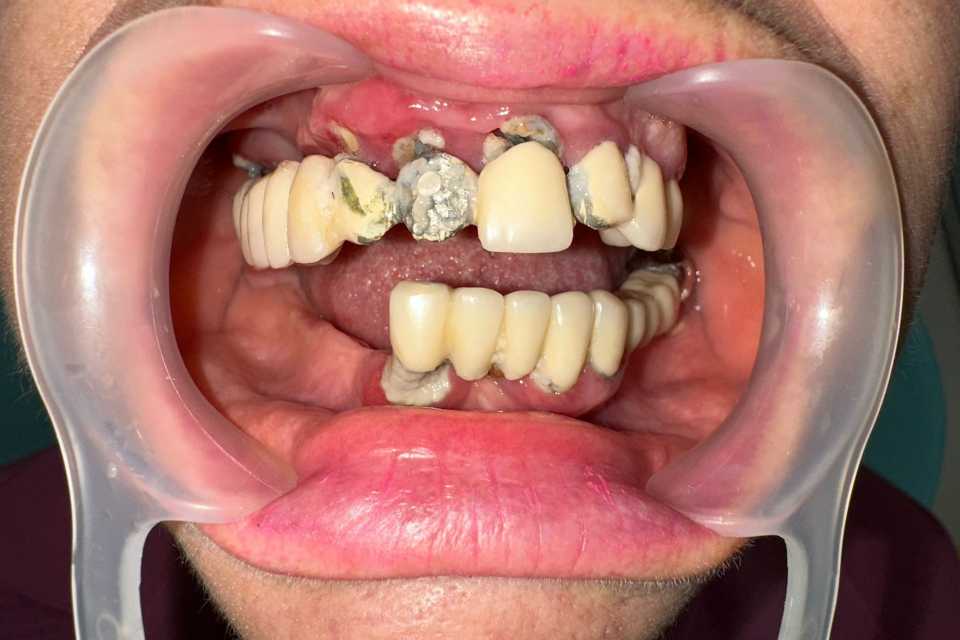

All on 6, implanturi orale speciale pterigoide

Imaginile sunt prezentate în ordinea evoluției tratamentului, de la situația inițială la rezultatul final.